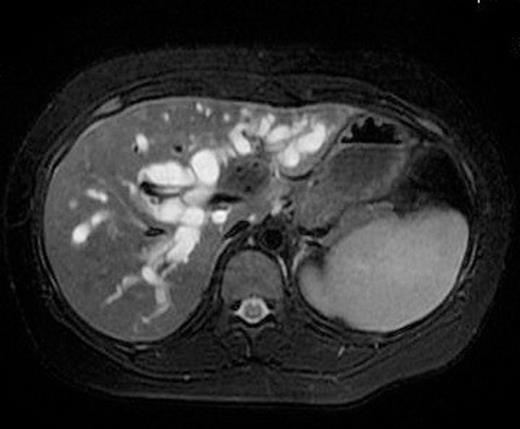

21 year old female patient presented with painless progressive jaundice of one month duration. She had generalized pruritus, severe loss of weight and loss of appetite. She had no other co-morbidity. On examination she had icterus and hepatomegaly. Laboratory investigations revealed evidence of obstructive jaundice with serum total bilirubin of 16 mg/dL and conjugated bilirubin 8.2 mg/dL. Other abnormal findings included elevations in serum alkaline phosphatase (789 IU/L), ALT (61 IU/L) and AST (40 IU/L). Tumour markers in the serum showed a mild rise in CA 19-9 (45 U/ml) whilst both AFP (4 ng/ml) and CEA (1.4 ng/ml) were within normal limits. Hepatitis serology (HBSAg and anti HCV) and HIV status were negative. Ultrasound revealed a collapsed gallbladder with bilateral intra hepatic biliary radical dilatation and a suspicious lesion at the hilum of liver. Subsequent MRI with MRCP (Figure 1) showed a definite lesion in the confluence of right and left major bile ducts with extension in to the left duct to involve secondary biliary radicles on that side, consistent with Type-3b Klatskin tumour according to Bismuth classification. The lesion was hypo-intense in T2, FIESTA and LAVA sequences of MRI and it showed moderate enhancement in venous phase. With the diagnosis of hilar CCA, patient was taken up for surgery after preoperative optimisation.

MRI of the liver showing lesion at the confluence of right and left hepatic ducts with extension in to the left duct.